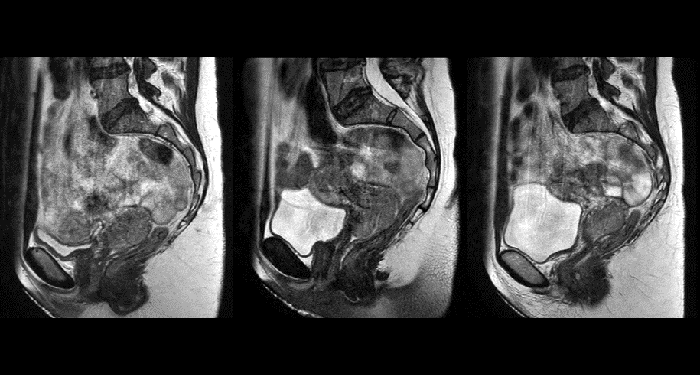

With its exceptional soft-tissue visualization capabilities and wide range of image contrasts, MRI has become a powerful tool to help more precisely define tumor boundaries. This is particularly important as it has been established that there is a high degree of uncertainty in target volume delineation, and it is even reported to represent the largest uncertainty in the entire radiotherapy process for most tumor sites**. Better visualization of the target area and nearby organs-at-risk is a key factor in enhancing target volume delineation. MRI’s expanding role also can be attributed to its functional imaging capabilities, which can inform both target characterization and treatment response.

Our innovative MRCAT (MR for Calculating ATtenuation) clinical applications lets you plan radiation therapy using MRI as primary imaging modality. Within just one, fast MR exam, MRCAT provides both excellent soft-tissue contrast for target and OAR delineation and CT-like density information for dose calculations.

This not only extends the benefits of MRI’s excellent soft-tissue contrast to radiotherapy planning, but it also eliminates arduous, error-prone CT-MRI registration from the process, reducing uncertainties and complexity.